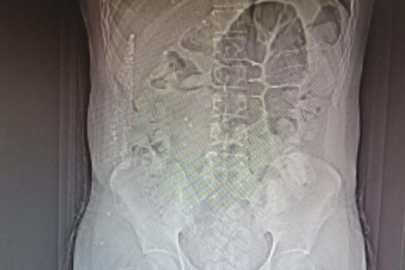

https://www.sozbursa.com

İl Emniyet Müdürlüğü Narkotik Suçlarla Mücadele Şube Müdürlüğü ile Kaçakçılık ve Organize Suçlarla Mücadele Şube Müdürlüğü ekiplerince yapılan ortak çalışmada; uygulama noktasında durdurulan, İran otobüsünde yolcu olarak bulunan İran uyruklu şüpheli M.K. (31) isimli kişiye yapılan tomografi çekiminde mide ve bağırsak kısmında uyuşturucu olabileceğini değerlendirilen çok sayıda yabancı cismin olduğu tespit edildi.

Yapılan tetkikler neticesinde M.K.’nın midesinden 64 parça halinde 711,86 gr gelen Afyon Sakızı ele geçirildi.